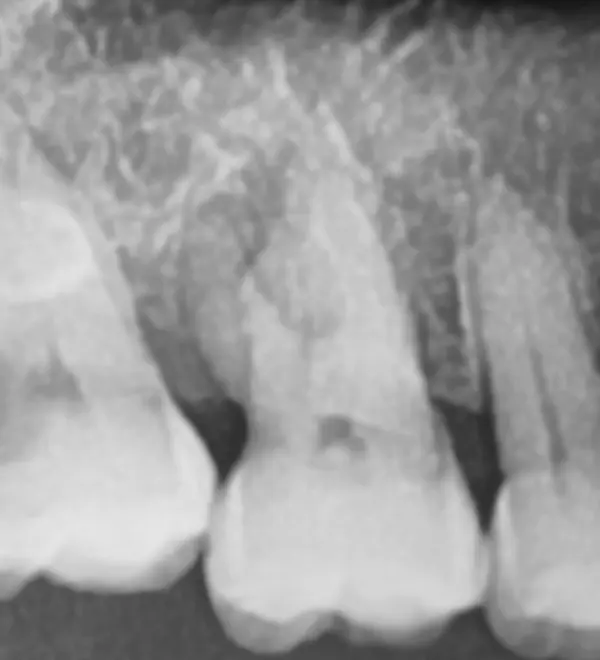

• Exercise 2

Dental x-ray, tooth and canal